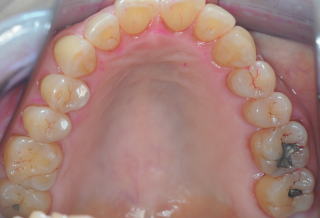

(図15)2015年7月27日、83歳。高年齢と残存歯数ばかりが問題視されているが、歯槽骨の状態、歯肉、Pocketの状態を含めた歯周病を評価すべきである

| MOBILITY | 0 | 0 | 0 | 0 | 0 | 0 | 0 | 0 | 0 | 0 | 0 | 0 | 0 | 0 |

| EPP(mm) | 3 | 3 | 3 | 3 | 3 | 2 | 2 | 2 | 2 | 2 | 3 | 3 | 3 | 3 |

歯周病治療38年経過:83歳(女性)残存歯数28本